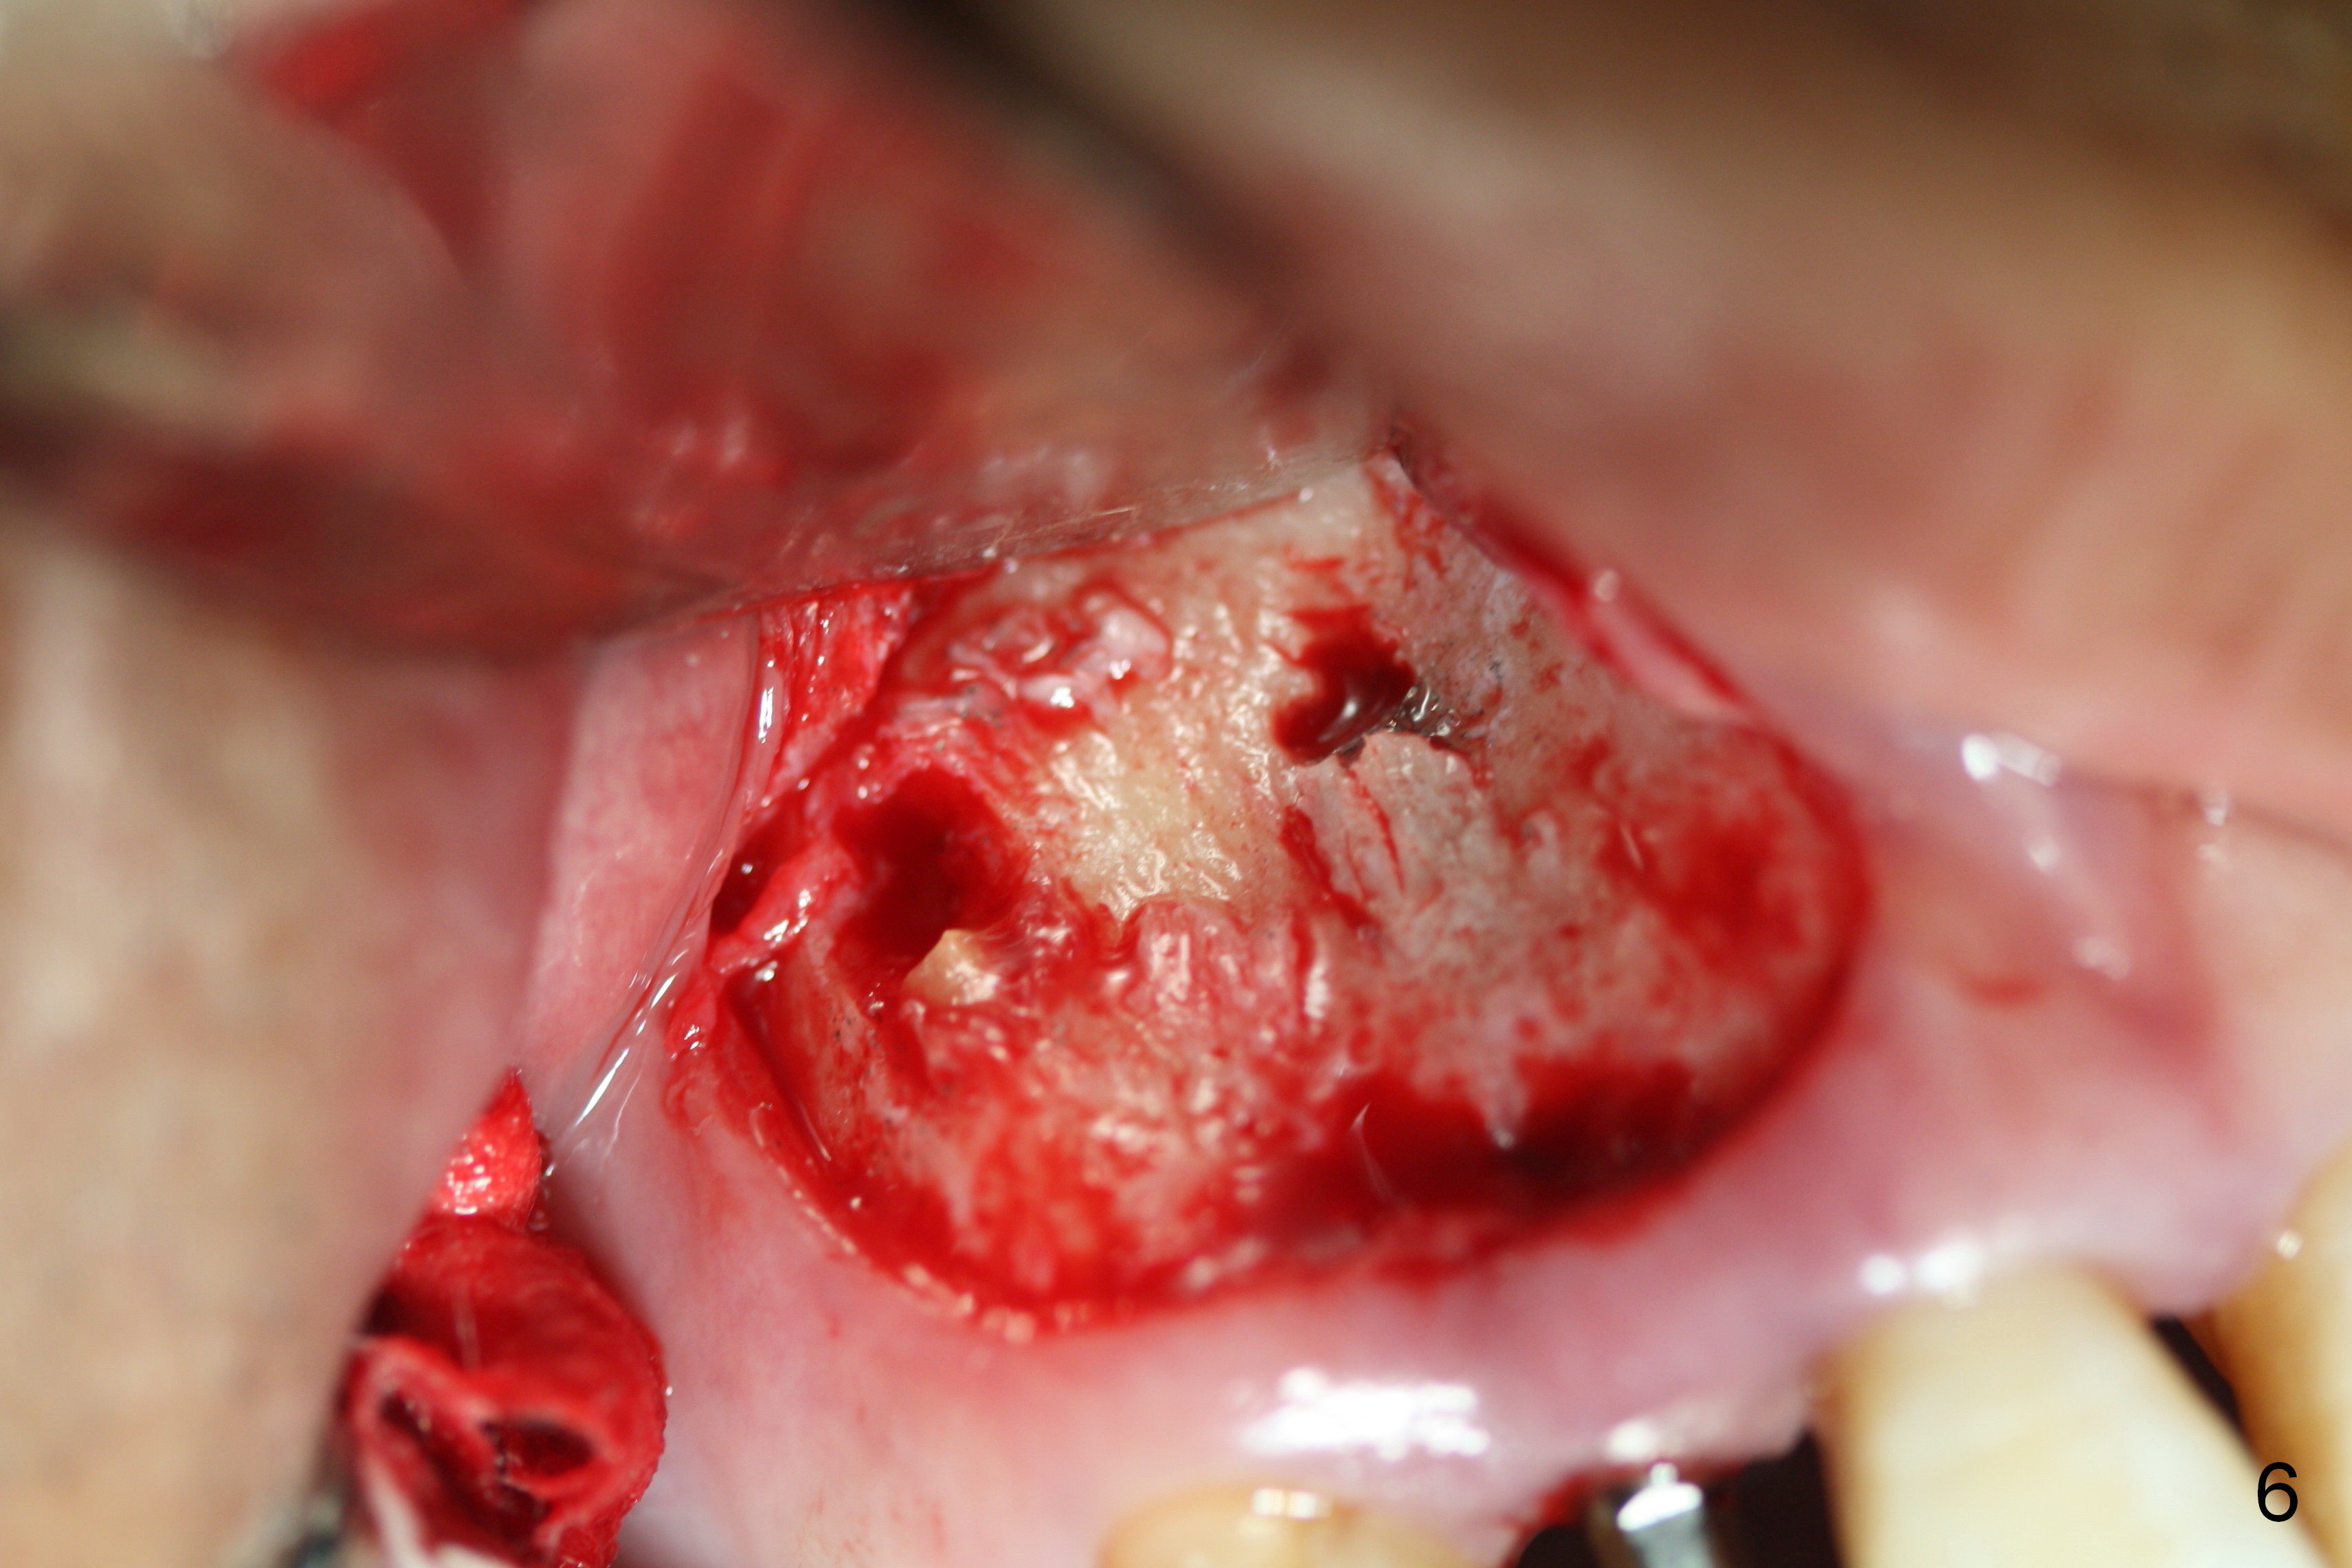

Preop exam shows the apparent wide ridge at #7 (Fig.1). What is ignored preop is the concavity in the apical buccal region (Fig.2 *). When a 3x16(4) mm 1-piece implant is being placed (Fig.3 *, flapless), the apical buccal plate vibration is felt. The biggest mistake is that initial osteotomy is ~ 6 mm shy of the implant length, partially because of 6 mm gingival height. Since the tooth #6 is symptomatic after RCT with paste overfill (Fig.4 >), apicoectomy is contemplated at #6 with exploration of the buccal plate at #7 (Fig.5). Since the implant appears to be long enough, implant apical resection is performed (Fig.6). Since there is coronal thread exposure due to previous periodontitis (Fig.7 <), bone graft is placed in these 3 defective areas after decortication.